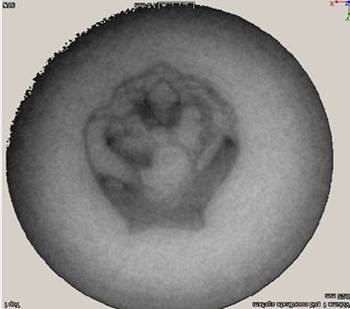

全長3mmのメダカCT画像。右図が、左図の赤線で示す方向の断層撮像で、断面は約0.5mm幅です。約10μm分解能が得られています。骨の代わりに柔らかい組織が見え、器官がはっきりと識別されています。